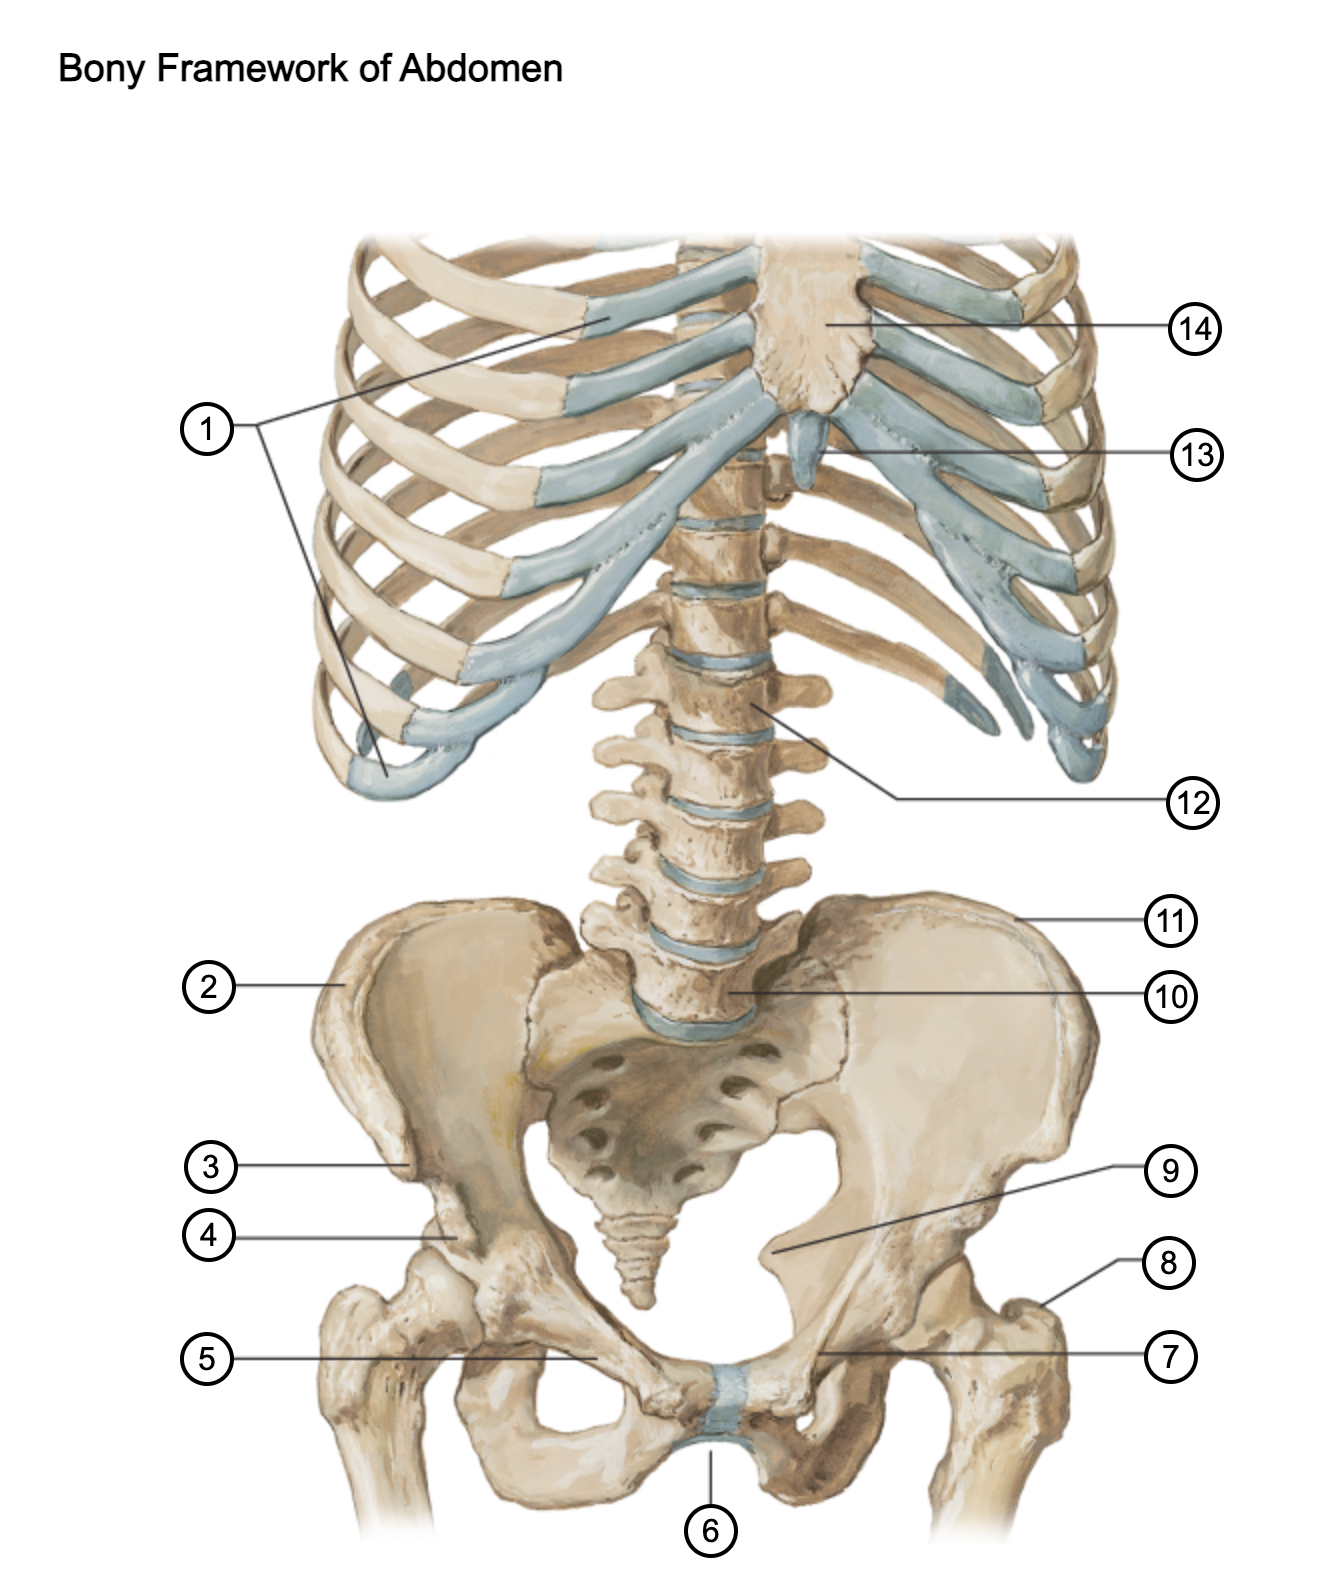

1

costal cartilages

2

iliac crest

3

anterior superior iliac spine

4

anterior inferior iliac spine

5

superior pubic ramus

6

pubic arch

7

pecten pubis

8

greater trochanter

9

ischial spine

10

L5 vertebra

11

iliac crest

12

L1 vertebra

13

xiphoid process

14

body of sternum